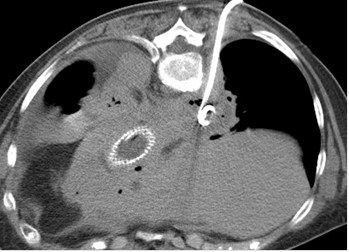

Cas 1 : Femme de 64 ans, transférée pour complication post fundoplicature de Nissen,

drainage sous scanner d’un abcès médiastinal postérieur droit.